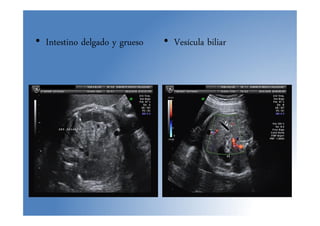

• Intestino delgado y grueso • Vesícula biliar

Anomalías sist. digestivo •Examen ecográfico, signos de sospecha ecográfica: – Intestino hiperecogénico – Ascitis – Ausencia de visualización del estómago por encima 16 sem. – Polihidramnios – Imágenes quísticas intraabdominales – Identificar la vesícula biliar a la derecha de la vena umbilical (a partir sem. 15 en casi 100% fetos) – Intestino delgado: a partir sem. 27 es normal encontrar pequeñas cantidades de líquido en su interior – Intestino grueso: se ve en 100% fetos a partir sem. 25

• Intestino delgadoy grueso • Vesícula biliar